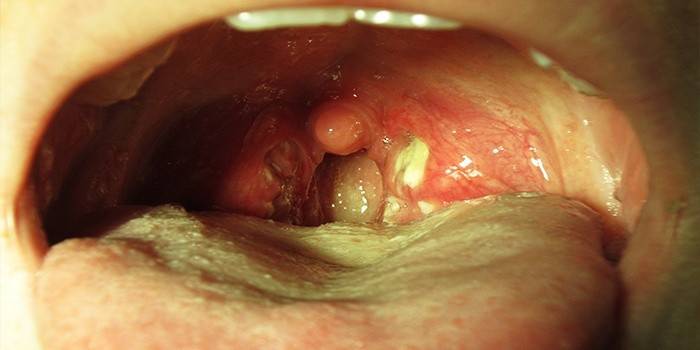

- pojawienie się ropnej płytki na migdałkach;

U niemowląt Staphylococcus aureus często znajduje się w gardle. Bakteria może być przenoszona przez mleko matki lub podczas porodu od matki, noworodki chorują. U dzieci zakażenie gronkowcem prowadzi do chorób przewlekłych. Bakterie mają tendencję do przemieszczania się przez ciało, powodując uszkodzenie różnych narządów i układów. U noworodków infekcja powoduje zapalenie gardła. Grzyb Candida często dołącza do Staphylococcus aureus.